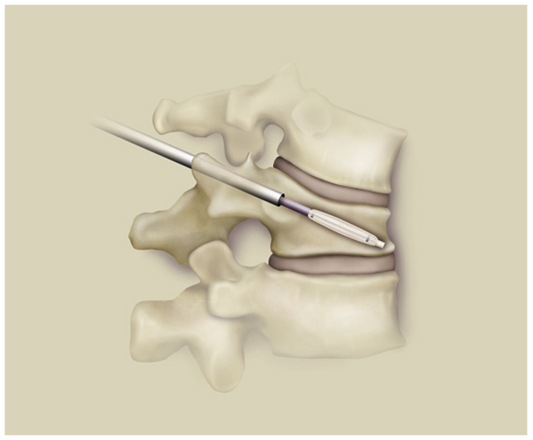

椎体成形术的技术要点

基本原理

通过工作通道置入球囊。

在体外通过压力泵给球囊加压。

负压取出球囊。

向空腔中注入骨水泥。椎体高度恢复,强度恢复。

03

手术入路

PKP入路有三类:

• 经椎弓根(推荐)

• 经椎弓根外

• 椎体侧方

经椎弓根外途径:一般为胸椎穿刺途径。进针点位于横突和上关节突交界处,在肋横关节间稍高于椎弓根外侧壁。

经椎弓根途径,一般为胸腰椎穿刺途径,建议适于T6以下(视实际椎弓根粗细而定),可有效避免血管神经损伤,有效防止填充剂向椎旁渗漏。进针方向为2点钟,15~20度角。